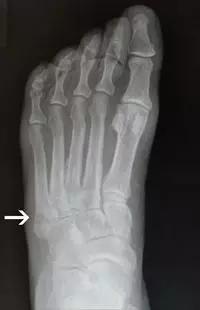

14.第五跖骨骨折

第五跖骨基底部骨折的不同类型:Stress 骨折;Jones 骨折:第五跖骨基底部以远 1 英寸内的骨折称为 Jones 骨折; Avulsion 骨折。

(来源:Radiopaedia)

Stress 骨折(来源:OrthoInfo-AAOS)

Jones 骨折正位片(来源:Radiopaedia)

Jones 骨折斜位片(来源:Radiopaedia)

第五跖骨骨折还有 dancer’s fracture。

dancer’s fracture 正位片(来源:footEducation)

dancer’s fracture 侧位片(来源:footEducation)